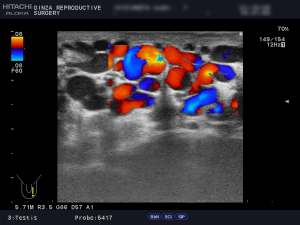

陰嚢のエコー検査の画像と解説

(例)左側2画面のエコー検査の画像です。

左の静脈径は、6.8mm 6.2mm 4.5mm 4.8mm 4.7mm。

ドップラで安静でも逆流著明、腹圧でさらに増強していました。

以上の所見より、診断は左側グレード3の精索静脈瘤です。